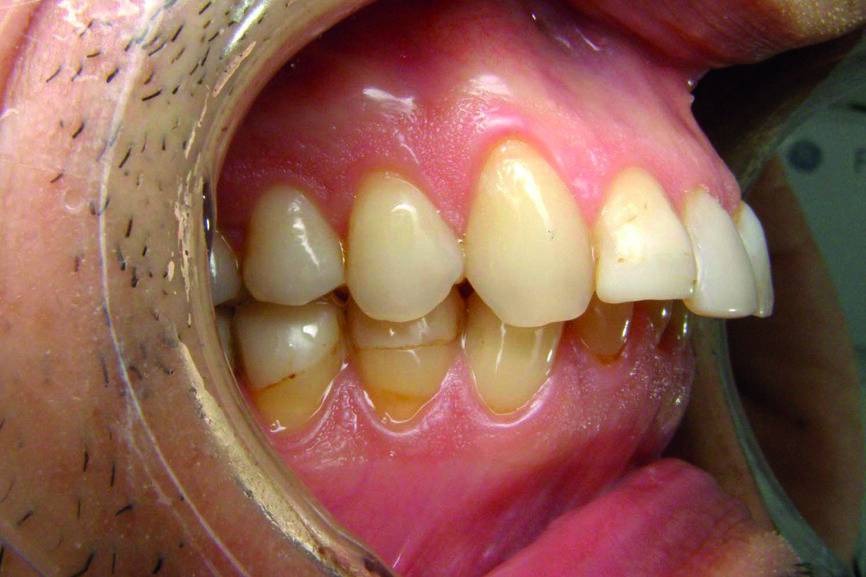

Examen des arcades

D’un point de vue dentaire le patient présente une Classe II division 1, avec une classe II molaire complète et une classe II canine.

- Présence d’un overjet et d’une supraclusion résiduelle.

- L’arcade supérieure est régulière mais les incisives sont en vestibulo version importante.

- L’arcade inférieure présente un encombrement dans le secteur antérieur associé à une version vestibulaire.

- Les milieux correspondent.